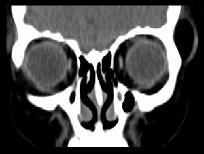

问题 女,31岁,在左眶外上缘发现一包块,质软,余所见无明显异常.如图所示病灶应诊断为()

选项 A.畸胎瘤 B.错构瘤 C.脂肪瘤 D.表皮样囊肿 E.淋巴管瘤

答案 C